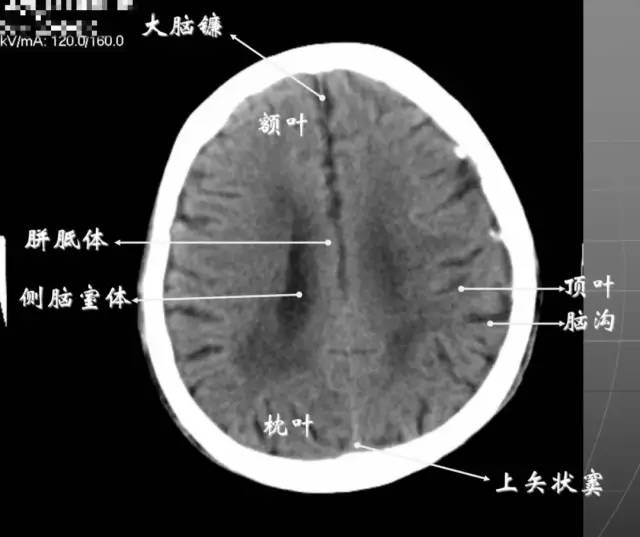

6、侧脑室上部层面内侧壁侧脑室体部被胼胝体分开,侧脑室体部的外方为顶叶,顶枕沟及中央沟将大脑为为额、顶、枕叶。

7、大脑皮质下部层面(半卵圆中心层面)在胼胝体和侧脑室上方,大脑镰自前向后贯穿中线。白质部分为半卵圆中心,额叶范围缩小,顶叶所占比例扩大,枕叶基本消失。

半卵圆中心:位于胼胝体上方,由左右大脑半球髓质形成的有髓纤维,对称位于大脑镰两侧区域。

8、大脑皮质上部层面(半卵圆区上部层面)已近颅顶,大脑镰清晰可见,其旁的脑灰质和脑沟十分清楚。顶叶较小,额叶较小。

放射冠:是内囊到大脑皮质间的放射状纤维白质。